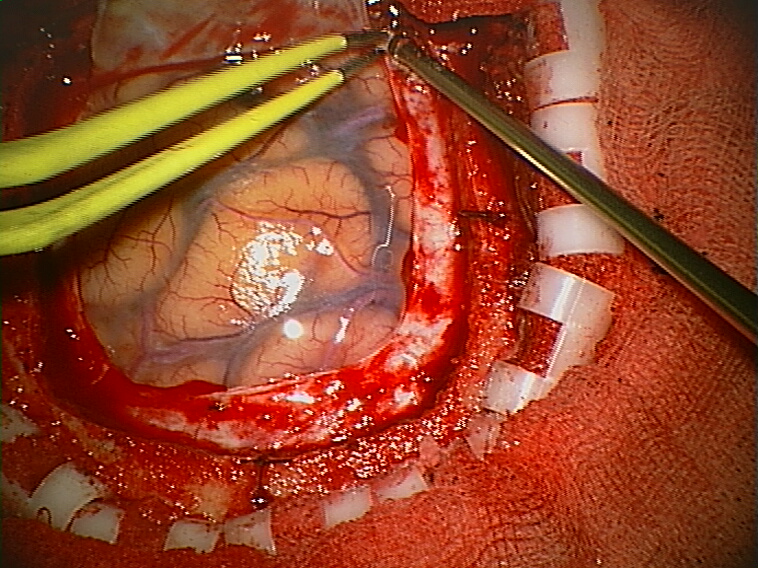

‘Tumours like this grow into the brain instead of displacing it, the tumour cells pushing into the brain’s soft substance, weaving their way between the nerve fibres and the brain cells of grey matter. The brain can go on working for a while even though the tumour cells are boring into it like deathwatch beetles in a timber building, but eventually, just as the building must collapse, so must the brain.’

One silver lining to Marsh’s book is that you learn that some famously intimidating tumours can be benign. The huge golf-ball tumour that appears on brain scans in TV serials and films is often not the short straw in the realm of brain tumours. These tumours are mostly external to the brain which essentially sit on it and decompress it – they displace the brain, which can cause death from excess pressure. These however can be removed and the patient can make a full recovery. The tumour to fear is one that will appear on a scan like a dark smudge. This is invasive and may alter everything from your personality to your vital senses before killing you. These tumours are therefore much harder to treat, and removal involves careful manoeuvring around critical brain tissue. Marsh’s accounts of these surgeries are often harrowing.